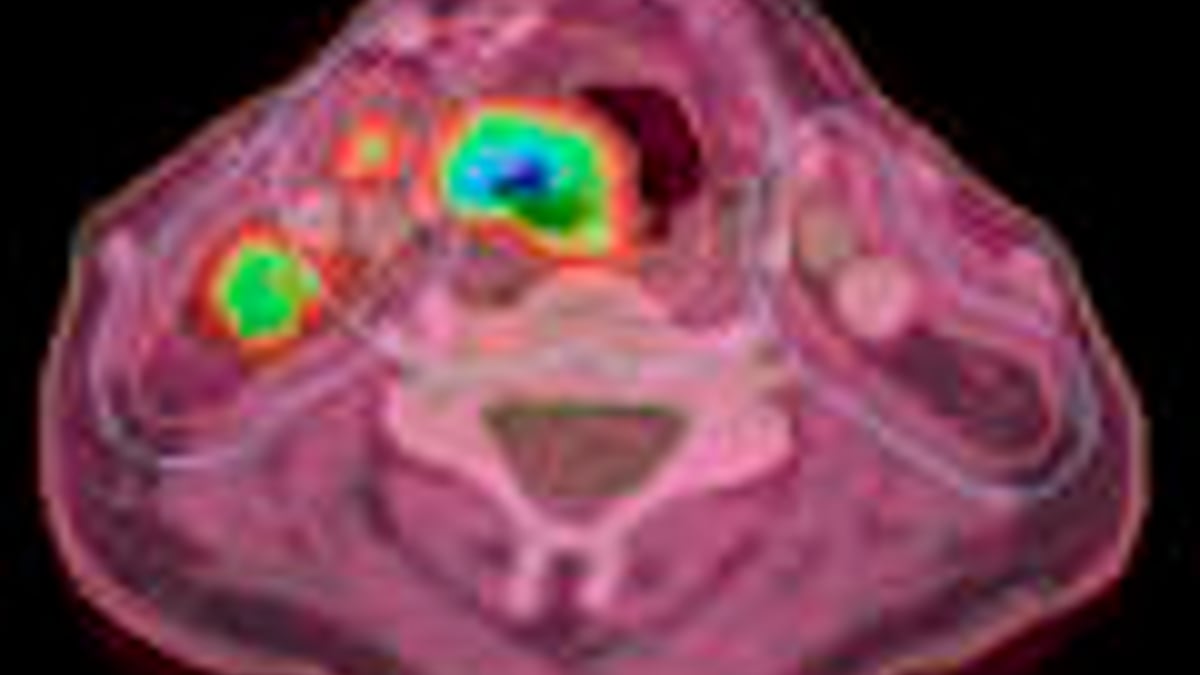

Bilden ovan visar en halstumör (det stora blågröna området i mitten) och två lymfkörtelmetastaser. Tack vare PET får man även biologisk information vilket är viktigt både vid diagnostik och dosplanering.